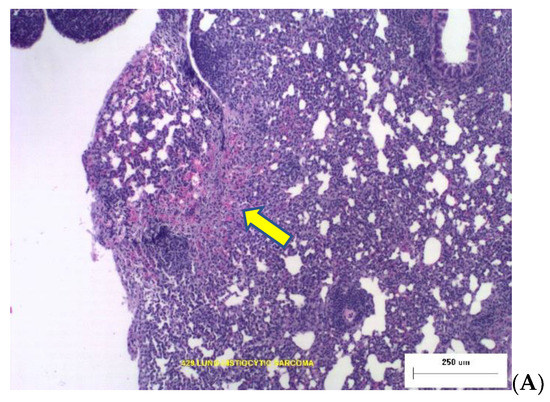

Two photomicrographs are included in Figure 2 illustrating the types of dose-dependent lung pathology observed 16-months after exposure to Silicon ions.

Figure 2.

Representative photomicrographs of lung tumor histopathology at necropsy 16 months post irradiation. (A) The yellow arrow points to Broncho-Alveolar Adenoma with adjacent normal tissue from an animal that was irradiated with 0.04 Gy Silicon. (B) Histiocytic Sarcoma in lung tissues from animal exposed to 0.16 Gy Silicon ions.